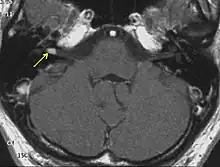

NF2 is a genetically transmitted condition. Diagnosis is most common in early adulthood (20–30 years); however, it can be diagnosed earlier. NF2 can be diagnosed due to the presence of a bilateral vestibular schwannoma, or an acoustic neuroma, which causes a hearing loss that may begin unilaterally.[15] If a patient does not meet this criterion of diagnosis, they must have a family history of NF2, and present with a unilateral vestibular schwannoma and other associated tumors (cranial meningioma, cranial nerve schwannoma, spinal meningioma, spinal ependymomas, peripheral nerve tumor, spinal schwannoma, subcutaneous tumor, skin plaque). This being said, more than half of all patients diagnosed with NF2 do not have a family history of the condition.[15] Although it has yet to be included into clinical classification, peripheral neuropathy, or damage to the peripheral nerves, which often causes weakness, numbness and pain in the hands and feet, may also lead to a diagnosis of NF2. In children, NF2 can present with similar symptoms, but generally causes "visual disturbances (cataracts, hamartomas), skin tumors, mononeuropathhy (facial paresis, drop foot), symptomatic spinal cord tumors, or non-vestibular intracranial tumors".[15]

Bilateral vestibular schwannomas are diagnostic of NF2.[16]

- Detection of bilateral acoustic neuroma by imaging-procedures